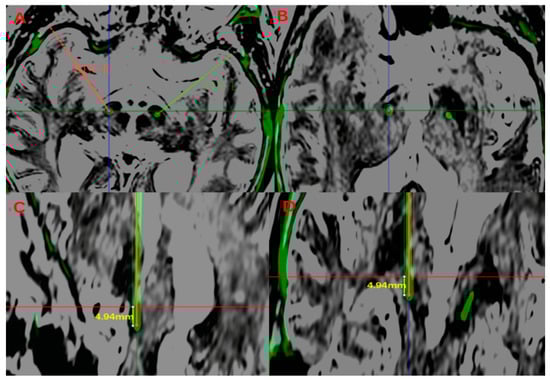

| Post-Lead Length (mm) | MER Length (mm) | d (mm) | Post-Lead Length vs. MER Length | |

| LA (n = 43) | 4.69 ± 1.14 | 5.48 ± 1.39 | 1.19 ± 0.58 | T = −4.27 p = 0.001 |

| GA (n = 40) | 4.47 ± 1.13 | 4.38 ± 1.43 | 1.18 ± 0.57 | T = 0.50 p = 0.61 |

| p | 0.38 | 0.001 | 0.95 |